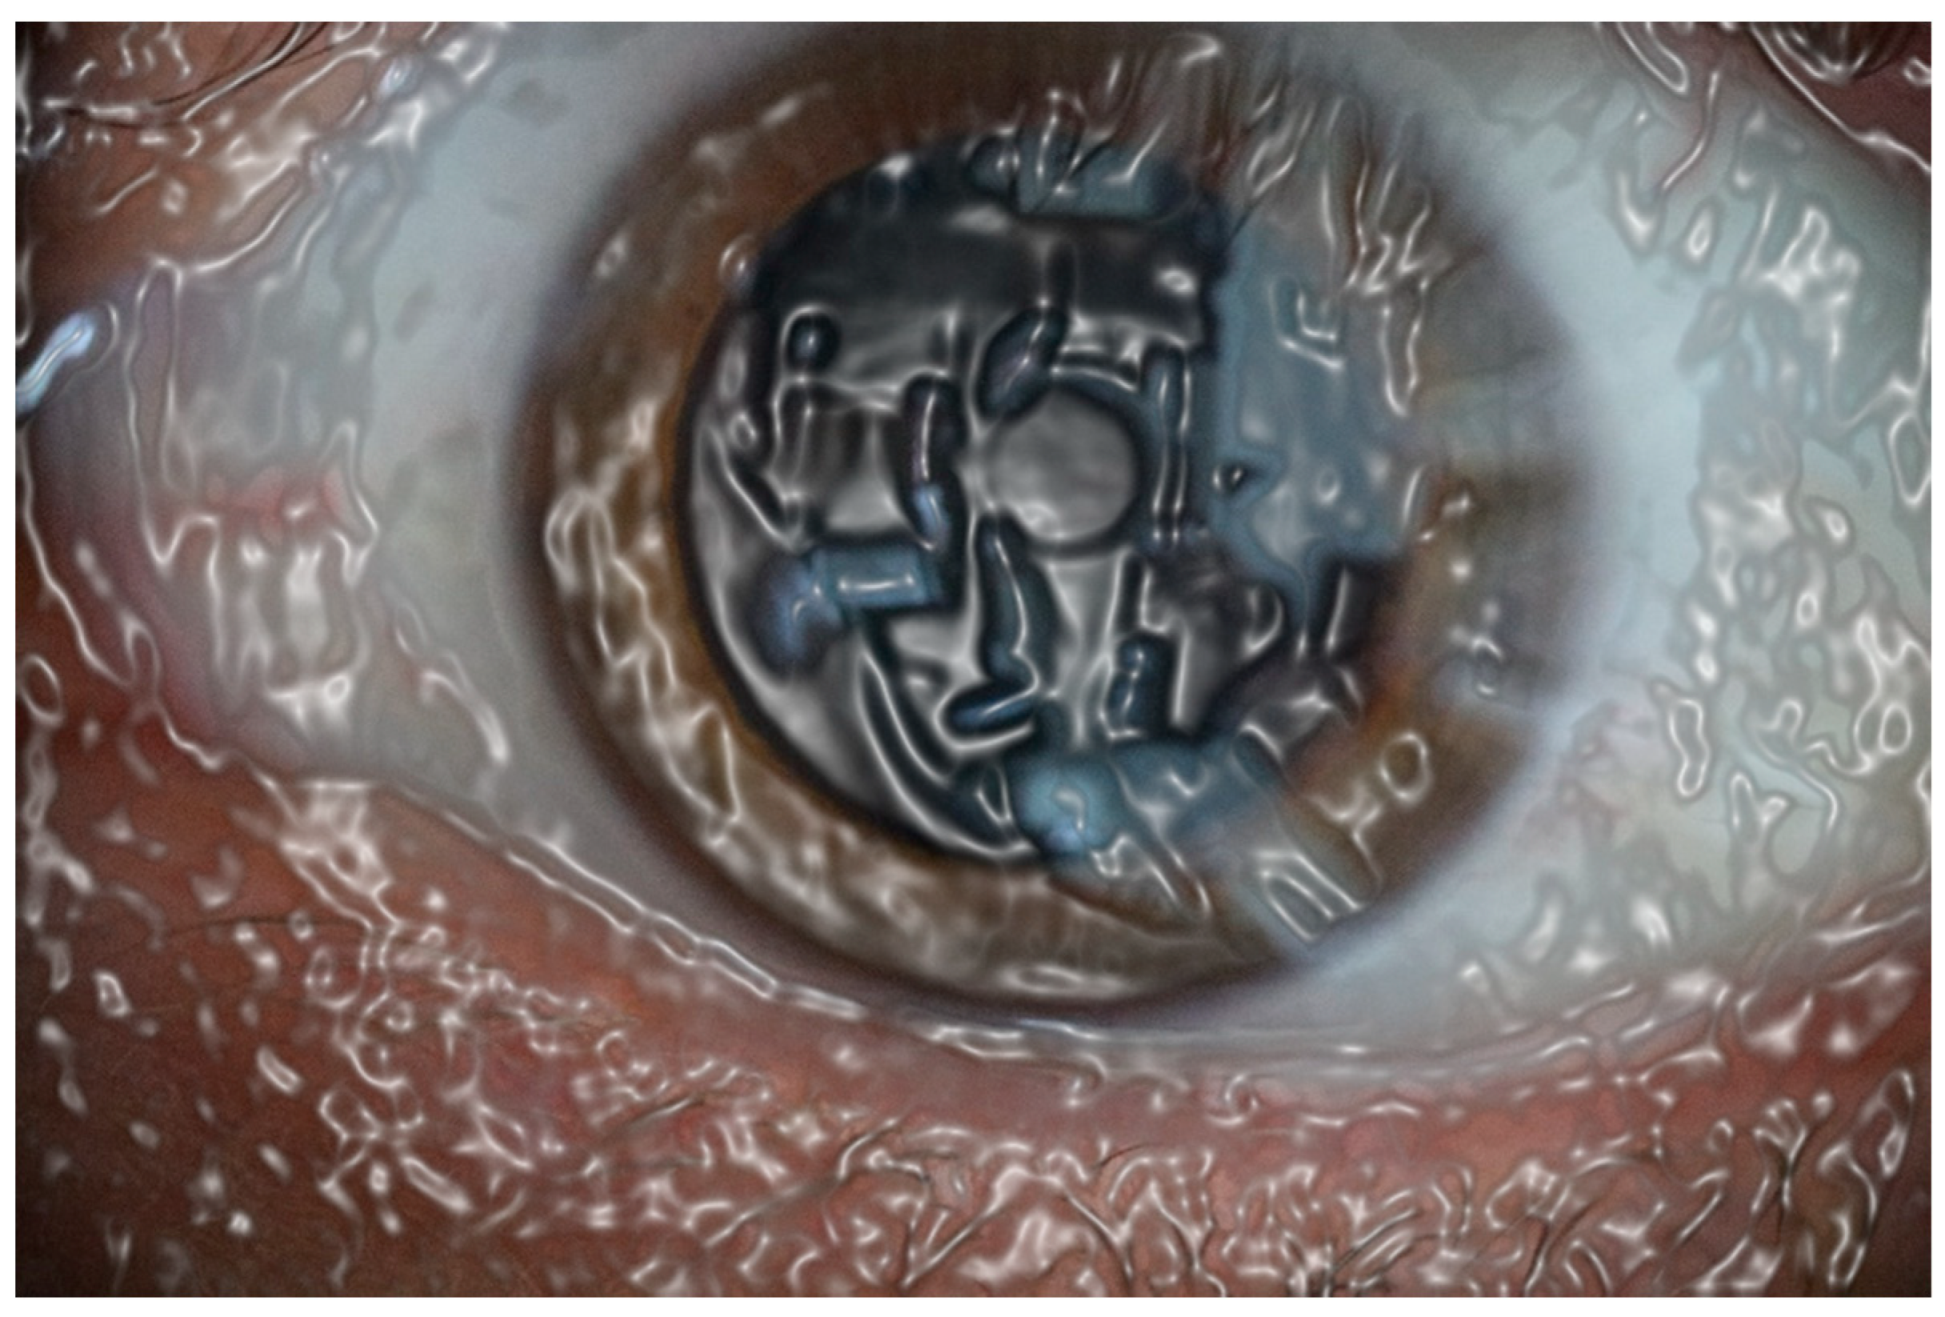

Figure 2. This photographic computer-assisted effect gives an approximate idea of the thousands or millions of cells that normally conform the ocular surface, but cell respiration means that only expels CO2, but it cannot do something approximate to oxygen absorption, like the lung that does not absorbs atmospheric oxygen, and only expels CO2.